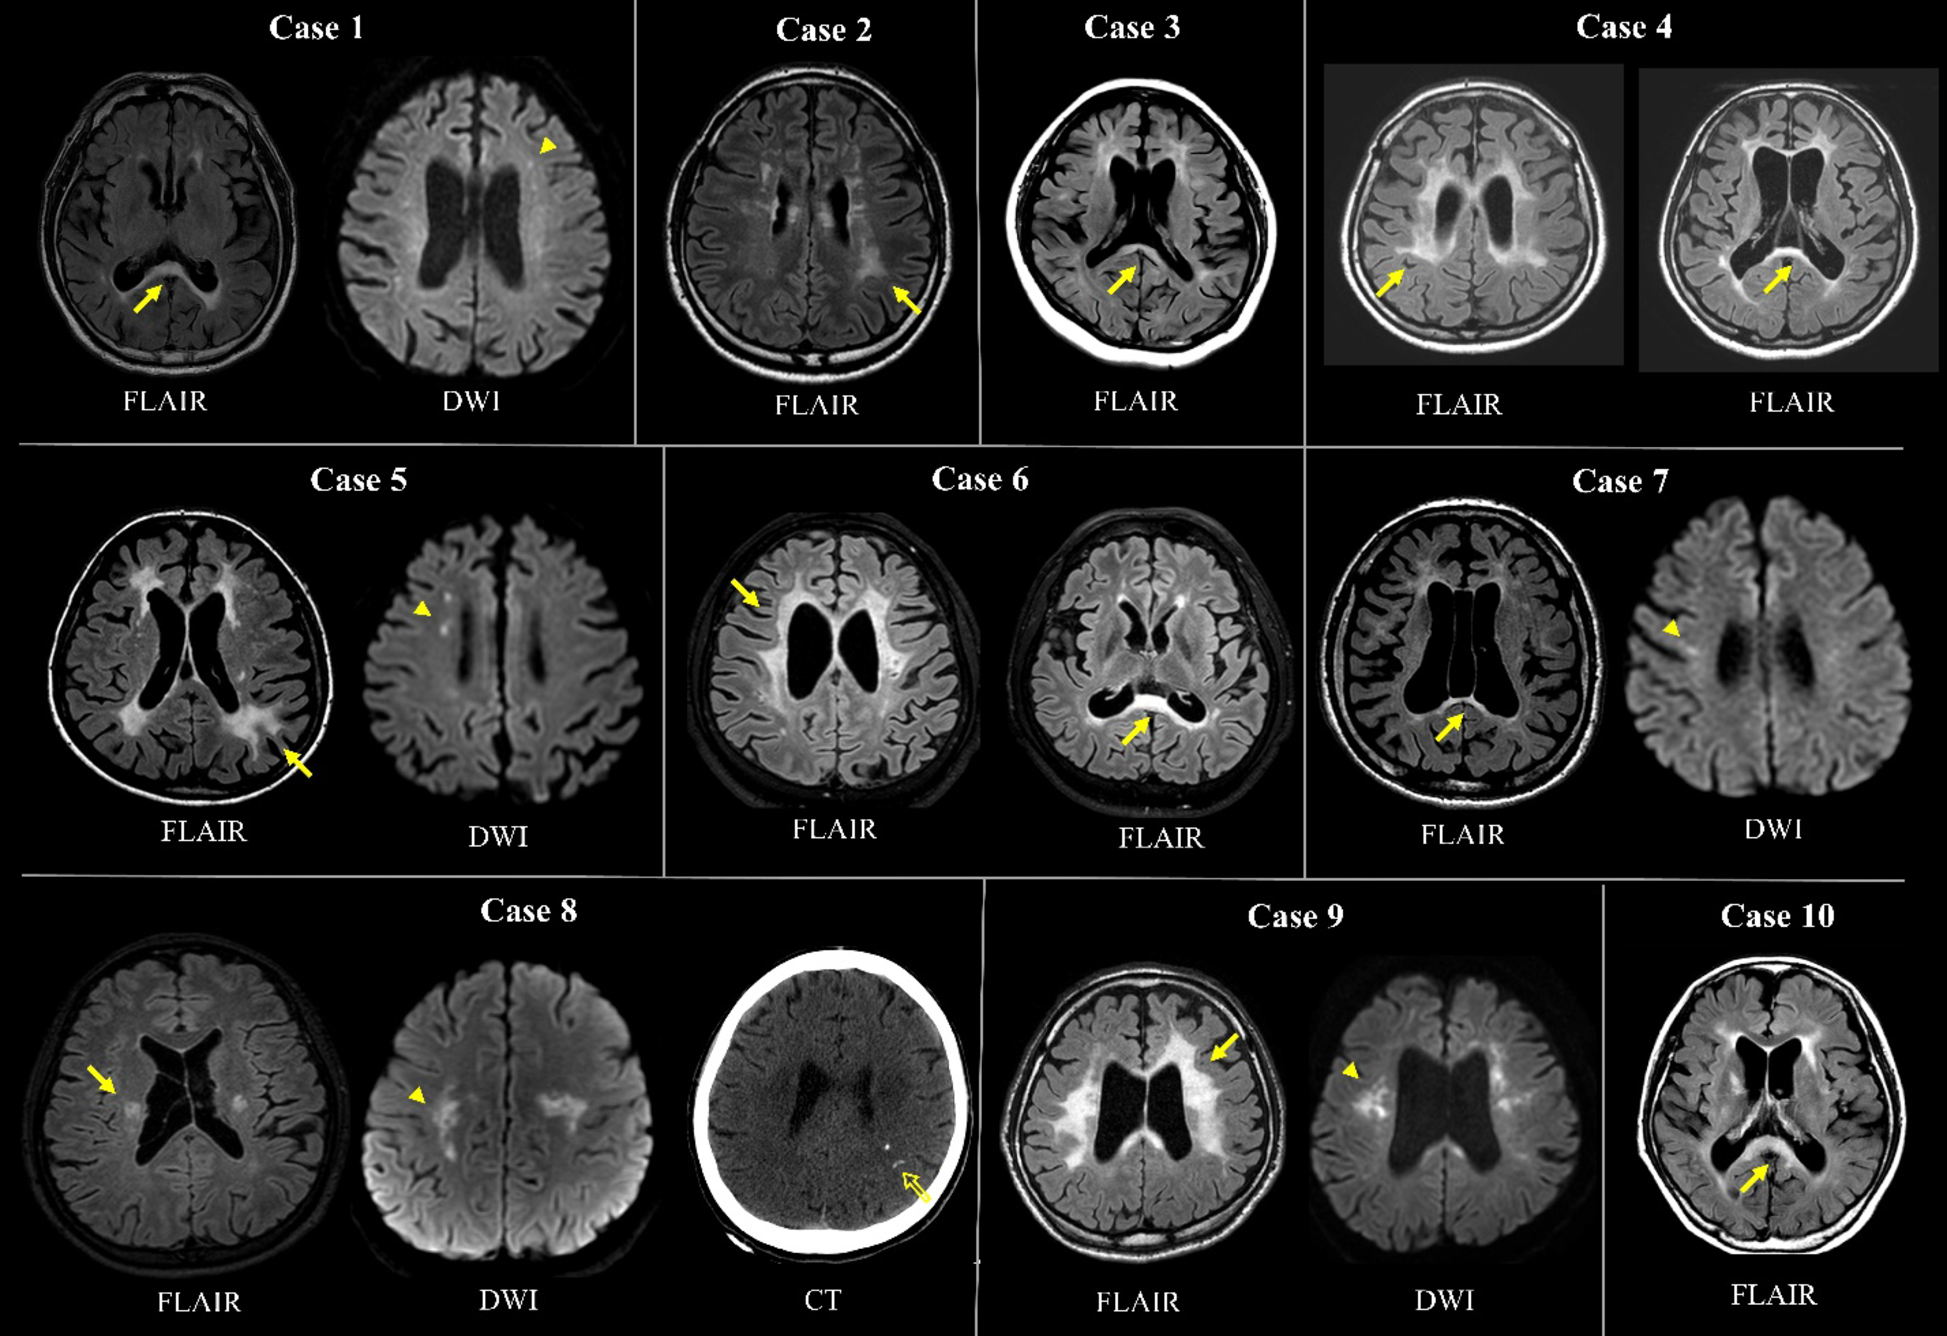

Neuroimaging findings of 10 ASLP cases.